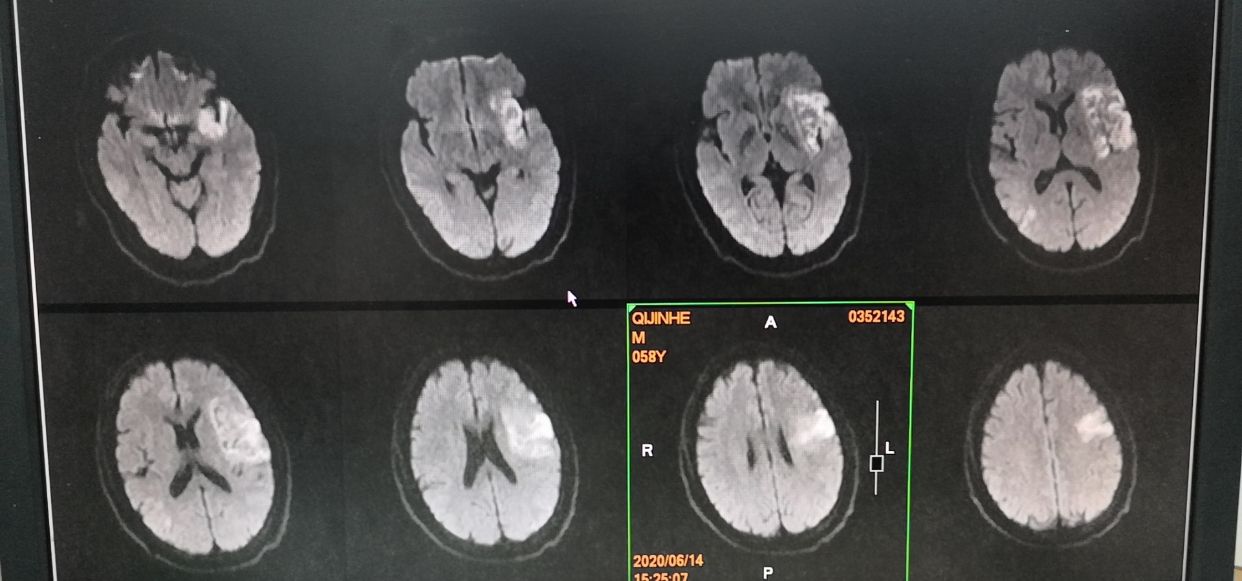

术后3天核磁

术后五天